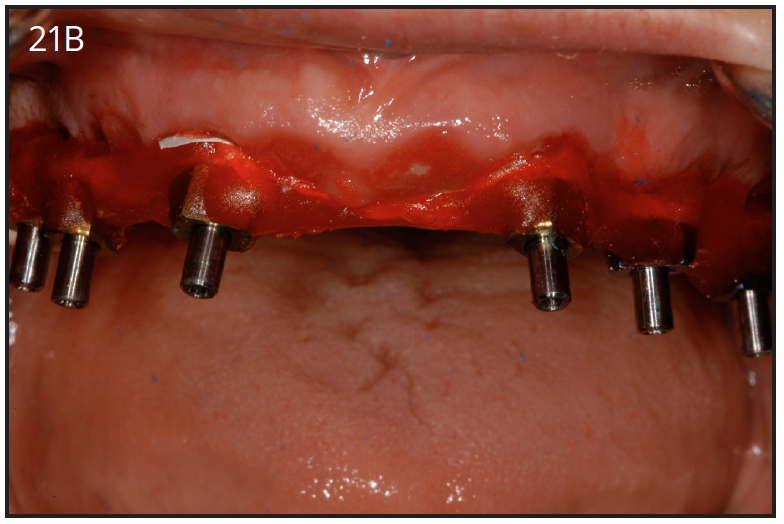

After 4 to 6 months of healing post-implant surgery, the final restoration is fabricated. An impression is taken either at implant level or at the abutment level to fabricate the final crown. The implant level impression records the implant position, so it needs to be very precise. An impression coping is screwed onto the implant to be transferred into the impression. The copings are utilized for a closed-tray technique or open tray technique. The closed tray technique may be used mostly with one implant, but the open-tray technique is used for multiple implants, when different implant angles exist. (Figures 21A, 21B) With either technique, the impression material most often recommended is polyether.34 Bite registration, shade selection, and opposing models are collected in the usual manner, as for crown and bridge cases.

Figure 21B – Open tray impression copings connected with acrylic

Figure 21B